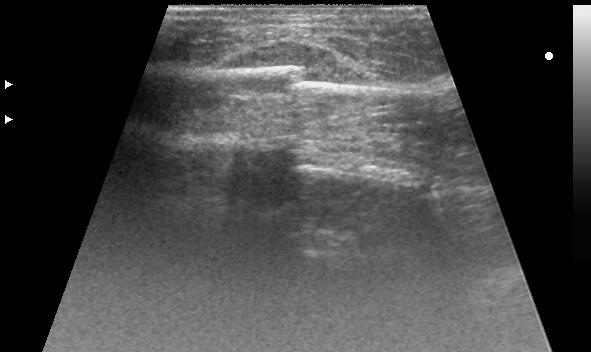

перелом ключицы, большой отек, травматолог хотел определится с тактикой...

по первому скану: перелом получается множественный? - кроме линии перелома впечатление о нарушении заднего контура ближе к границе среза (правда не в фокусе)